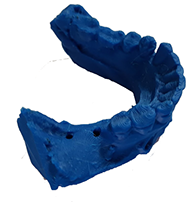

innovación dental

innovación dental